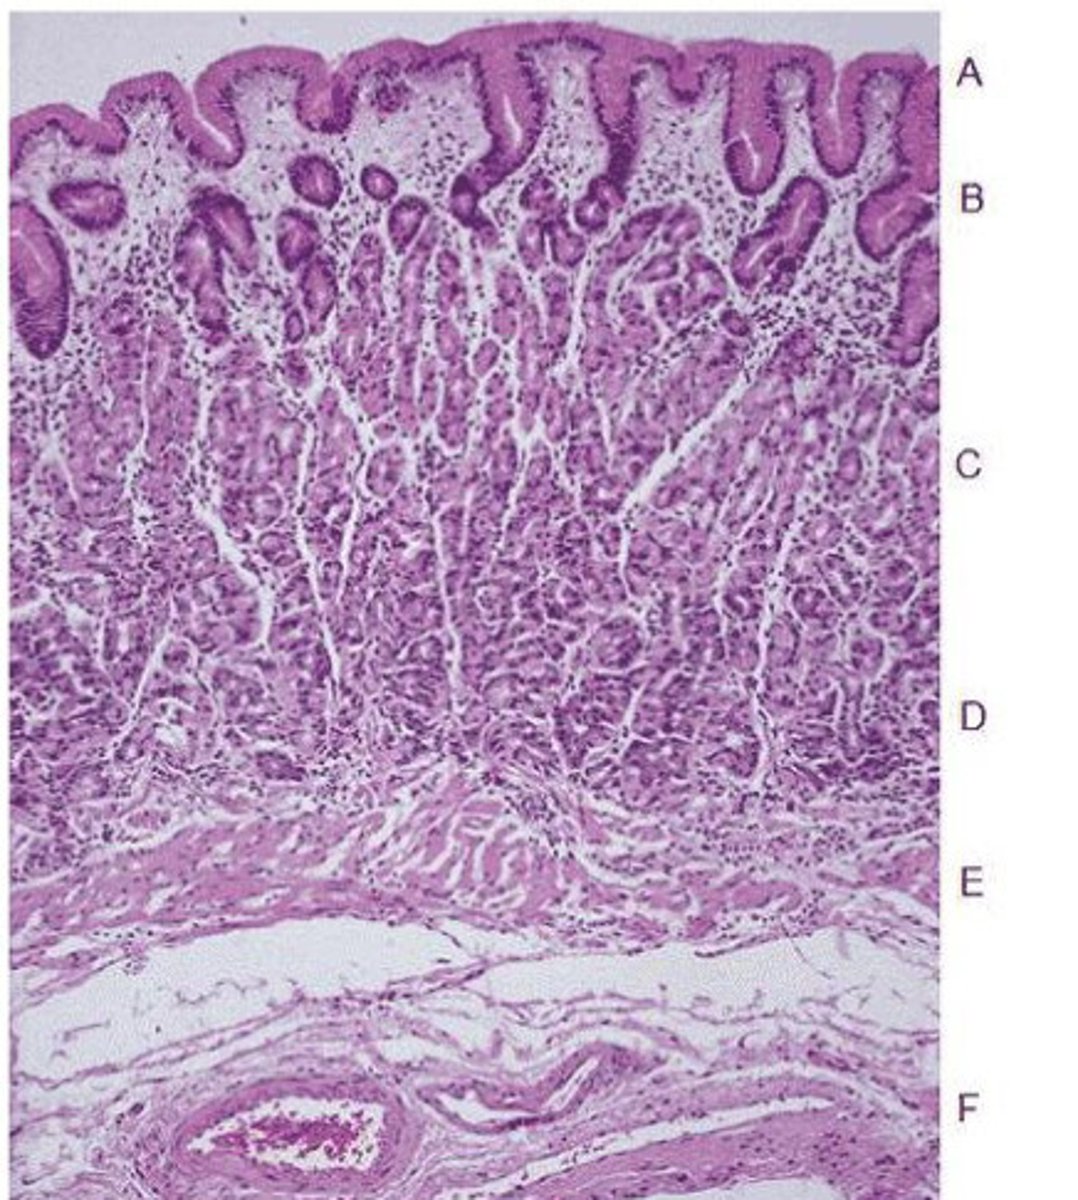

esophagus

name this entire structure (disregard green box)

adventitia

name structure E

muscularis externa

name structure D

submucosa

name structure c

Mucosa

Stratified squamous epithelium, lamina propria, muscularis mucosa

name structure B

What are the three layers of this structure?